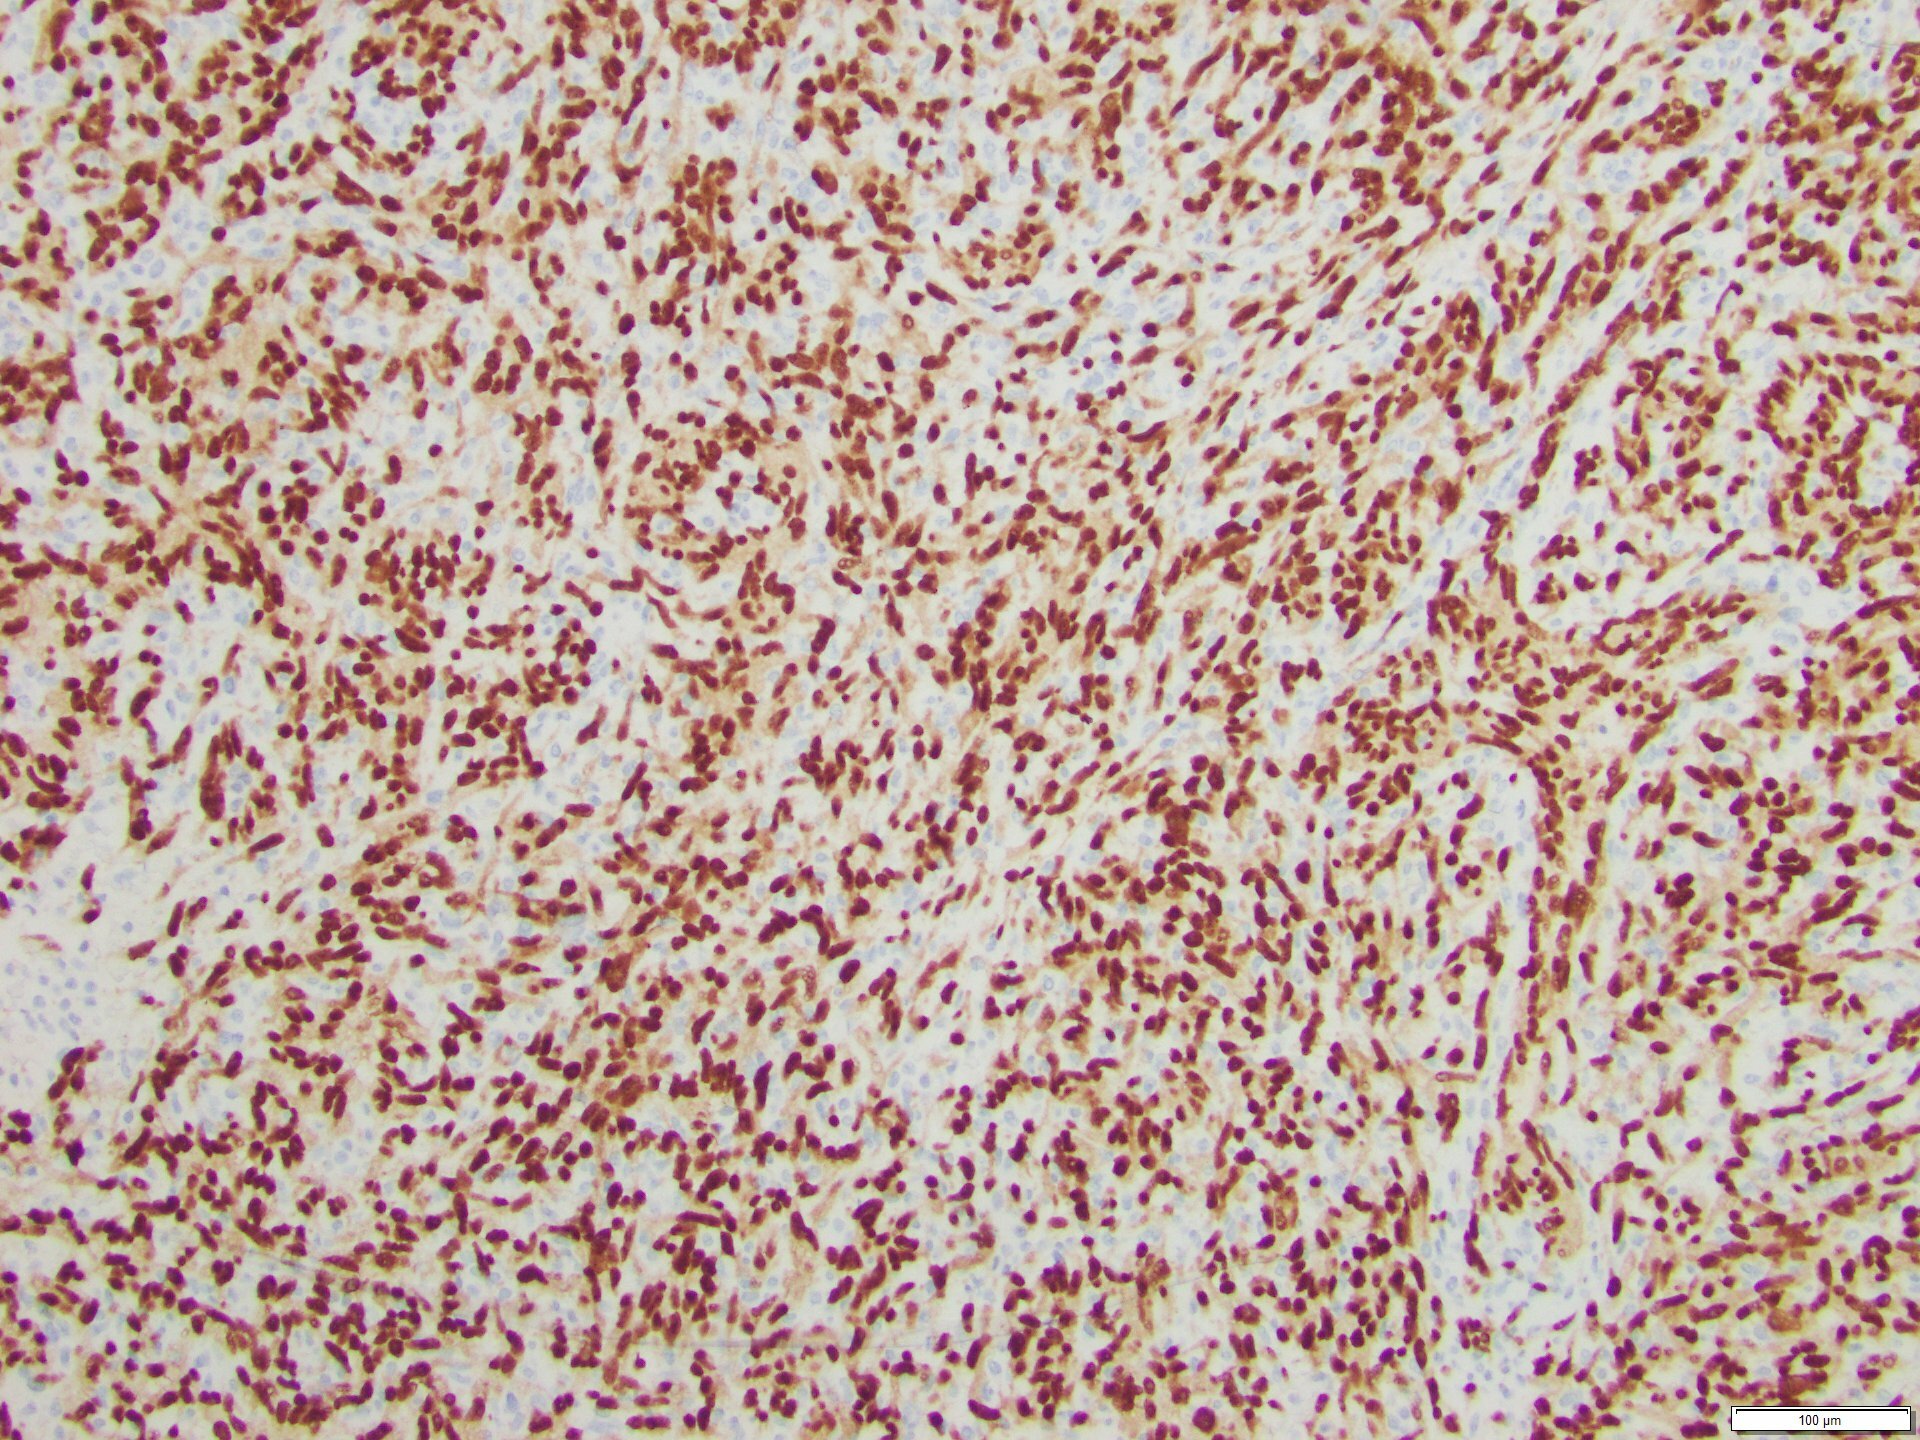

The skin lesion was completely excised and sent to pathology for diagnosis (Figures 1-3). The lesion is hypercellular with an infiltrative, predominantly solid, growth pattern in the dermis and subcutaneous tissue. It is highly vascular and has complex anastomosing and poorly formed vascular channels. The tumor cells are large, pleomorphic, have vesicular chromatin, and prominent nucleoli. There are frequent mitoses and extravasated red blood cells throughout. Immunohistochemistry shows the tumor cells are diffusely positive for ERG (Figure 4) and c-MYC (Figure 5) while negative for pan-cytokeratin (Figure 6) and GATA3. Subsequently, the patient underwent a left total mastectomy.